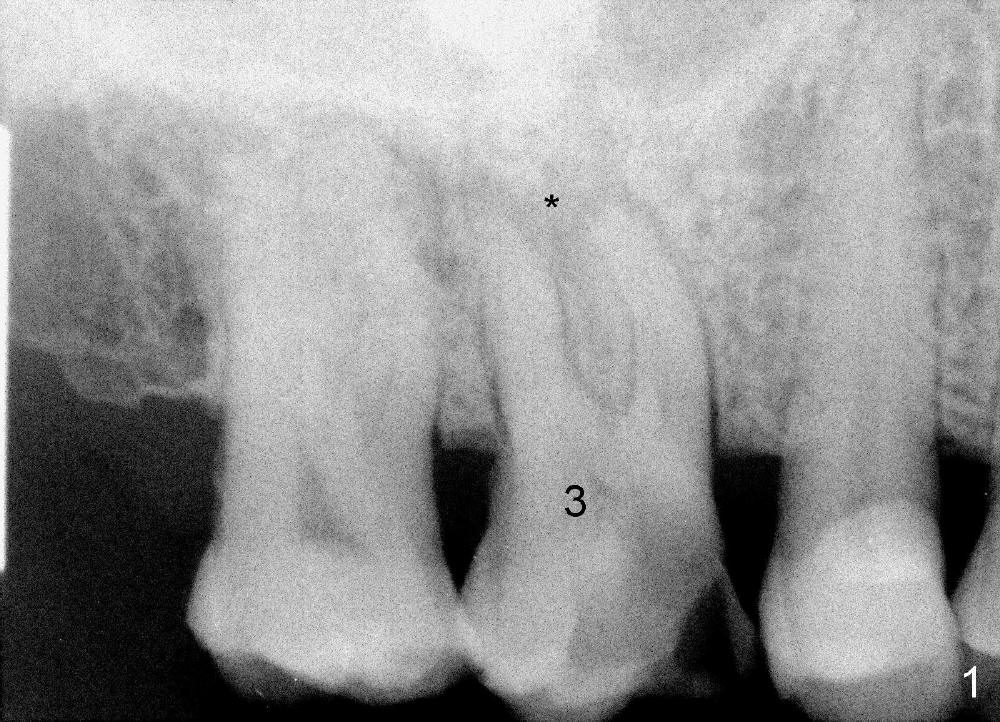

A 72-year-old man is a bruxer with #3 cusp fracture with chronic periapical radiolucency (Fig.1 *) and #4 acute crack. It appears reasonable to take care of emergency (#4 extraction and immediate implant (Fig.3-7: 4.5x20 mm, 45 Ncm)) followed by root canal therapy or extraction for #3. Eight (Fig.8) and 14 (Fig.9-11) days postop, the patient is doing fine and the wound heals normally. But he does not agree any treatment for #3, since it is asymptomatic in spite of a fistula associated with the tooth (Fig.8,9 >). Three months postop, the patient is still asymptomatic and is ready for #4 restoration since the tooth #28 cracks. Follow-up PA shows the persistent distal gap (Fig.12 >, as compared to Fig.4), accompanied with crestal bone resorption (*). Clinically the implant has mild mobility and light tenderness. The patient still refuses #3 treatment. It appears that the implant has failed to osteointegrate. In brief, do not place an immediate implant next to active infection.